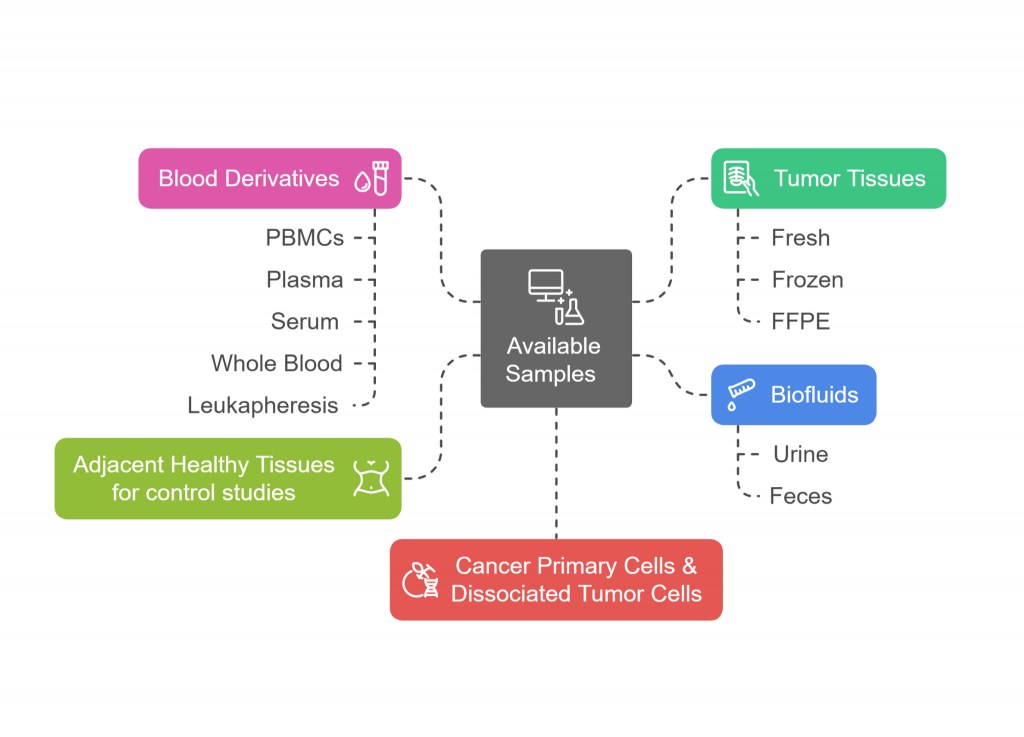

Dans le paysage actuel de l'oncologie de précision, l'accès à des échantillons biologiques de haute qualité et bien annotés est plus vital que jamais. Qu'il s'agisse de sang, de plasma, de sérum, d'ADN, d'ARN ou de tissus frais ou FFPE, l'intégrité et la pertinence clinique des échantillons biologiques influencent directement la fiabilité des résultats de la recherche et le succès de la découverte de biomarqueurs et du développement thérapeutique.

Chez CliniSciences, nous sommes spécialisés dans la fourniture d'un portefeuille complet d'échantillons dérivés de patients atteints de cancer, y compris des échantillons appariés et des collections longitudinales. Chaque échantillon provient d'une source éthique, est conservé de manière experte et est accompagné de métadonnées cliniques détaillées pour soutenir la recherche translationnelle et préclinique.

Échantillons disponibles